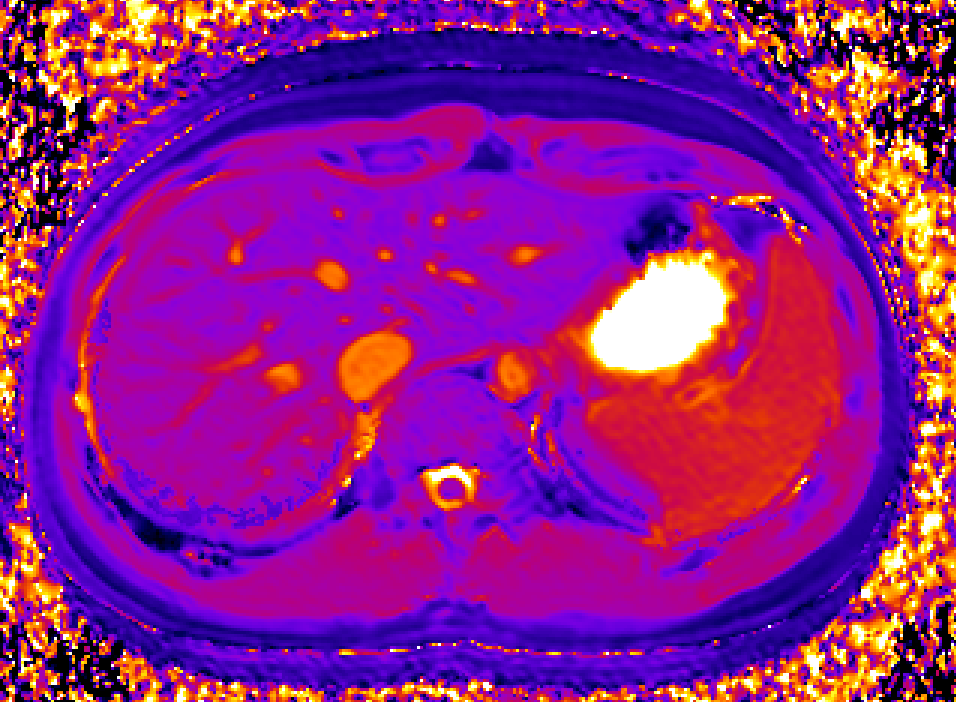

Bioxydyn uses dynamic gadoxetate-enhanced MRI to assess liver transporter function non-invasively. Gadoxetate is taken up by functioning hepatocytes and excreted into bile, allowing MRI to measure key aspects of hepatobiliary transport in vivo. By combining dynamic imaging with quantitative modelling, we can derive biomarkers of hepatocellular uptake and biliary excretion, alongside complementary measures such as relaxation time mapping.

This approach provides functional information that cannot be obtained from standard anatomical imaging or blood measurements alone. It is particularly relevant where changes in liver transport may affect drug exposure, clearance, or tissue accumulation.